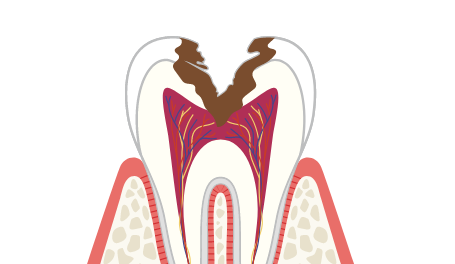

今までドックスベストセメントでカバーしきれない程に大きいむし歯だと、神経と口が露髄(神経の一部が外に出ている状態)してしまい、神経を取らざるを得ませんでした。

ですが、MTAセメントには膨張性があるため、露髄するようなむし歯でも完全に封鎮・殺菌できます。病状によっては使えませんが、少し大きめのむし歯でも削る部分を最小限に抑え、神経を残した治療が可能です。

神経は感覚(温度差など)を司る組織で、歯の中にある歯髄(しずい)という場所に走っています。歯髄の中には歯や歯茎に栄養を送る血管も走っていますが、歯の神経を抜くとこの歯髄も取り除かなければいけません。

ですが、歯髄を取ってしまうと歯の感覚器官がなくなってしまい、栄養も行き届かなくなってしまいます。神経を取ってしまうと平均的に15年で歯が折れてしまうと言われていて、たとえむし歯がなくなっても長く健康な歯を保つことは難しいでしょう。

むし歯治療では一般的に3回目の治療をする時、歯の神経にばい菌が入り神経を取る治療になると言われています。つまり、一度再発したむし歯の治療をする時は2回目の治療になり、神経を取る前の最後の治療になります。

神経を取った後、約15年すると歯が割れてしまうという報告もあるため、虫歯の再治療はとても慎重に行わなければいけません。